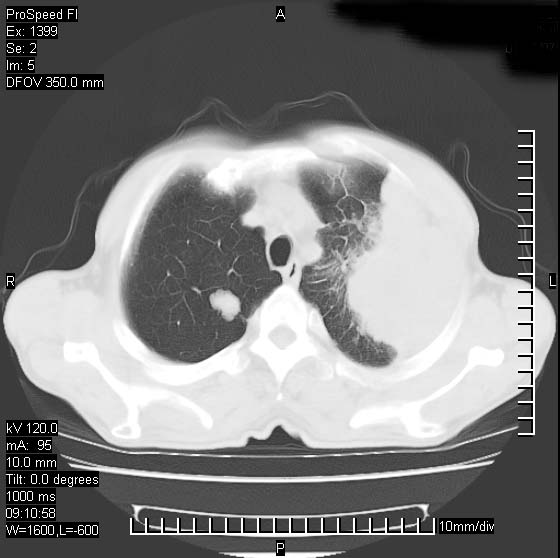

以下是引用rgsyyf在2007-1-19 11:05:00的发言:[br]左肺上叶见形态不规则巨大软组织肿块影,边缘呈分叶征,纵隔内隆突下见肿大淋巴结,右肺内另见一不规则结节影 .考虑:左肺周围性肺癌伴纵隔即右肺内转移.